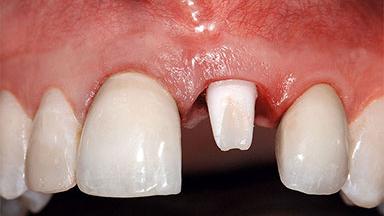

Replacement of a Missing Upper Left Central Incisor: Late Placement of an RC Bone Level Implant, CAD/CAM Zirconia Abutment

A healthy 37-year-old female patient was referred for a consultation on the replacement of missing tooth 21 with an implant-supported restoration. She stated that several years previously the tooth had been traumatically avulsed following a motor vehicle accident. The tooth was replaced with a three-unit fixed partial denture (FPD) immediately afterwards. Over time, she became disillusioned with the FPD and looked for a different option, including orthodontic therapy. She presented still in her orthodontic appliances, with the pontic sectioned free from the FPD but attached to the archwire. Her orthodontist felt that orthodontic treatment had been successfully completed, but nevertheless referred her before removing the appliances in case adjustments were necessary.

Abutment Type CAD/CAM

Defining Characteristics One missing tooth to be replaced by an implant-borne prosthesis

Bone Volume Deficient horizontally, allowing simultaneous augumentation

Esthetic Risk High